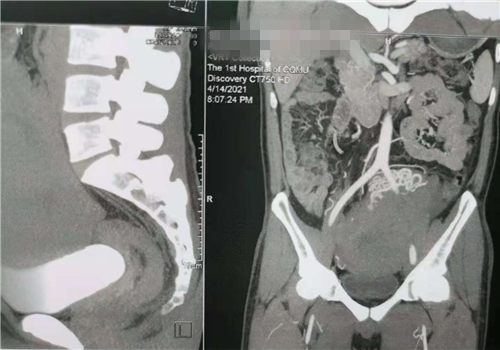

重庆高楼林立,重庆夜景华丽,重庆医护人员温情暖心……重庆给68岁的黑龙江患者张士诚(化名)留下的印象,将可能是终身难忘。本来是想到重...